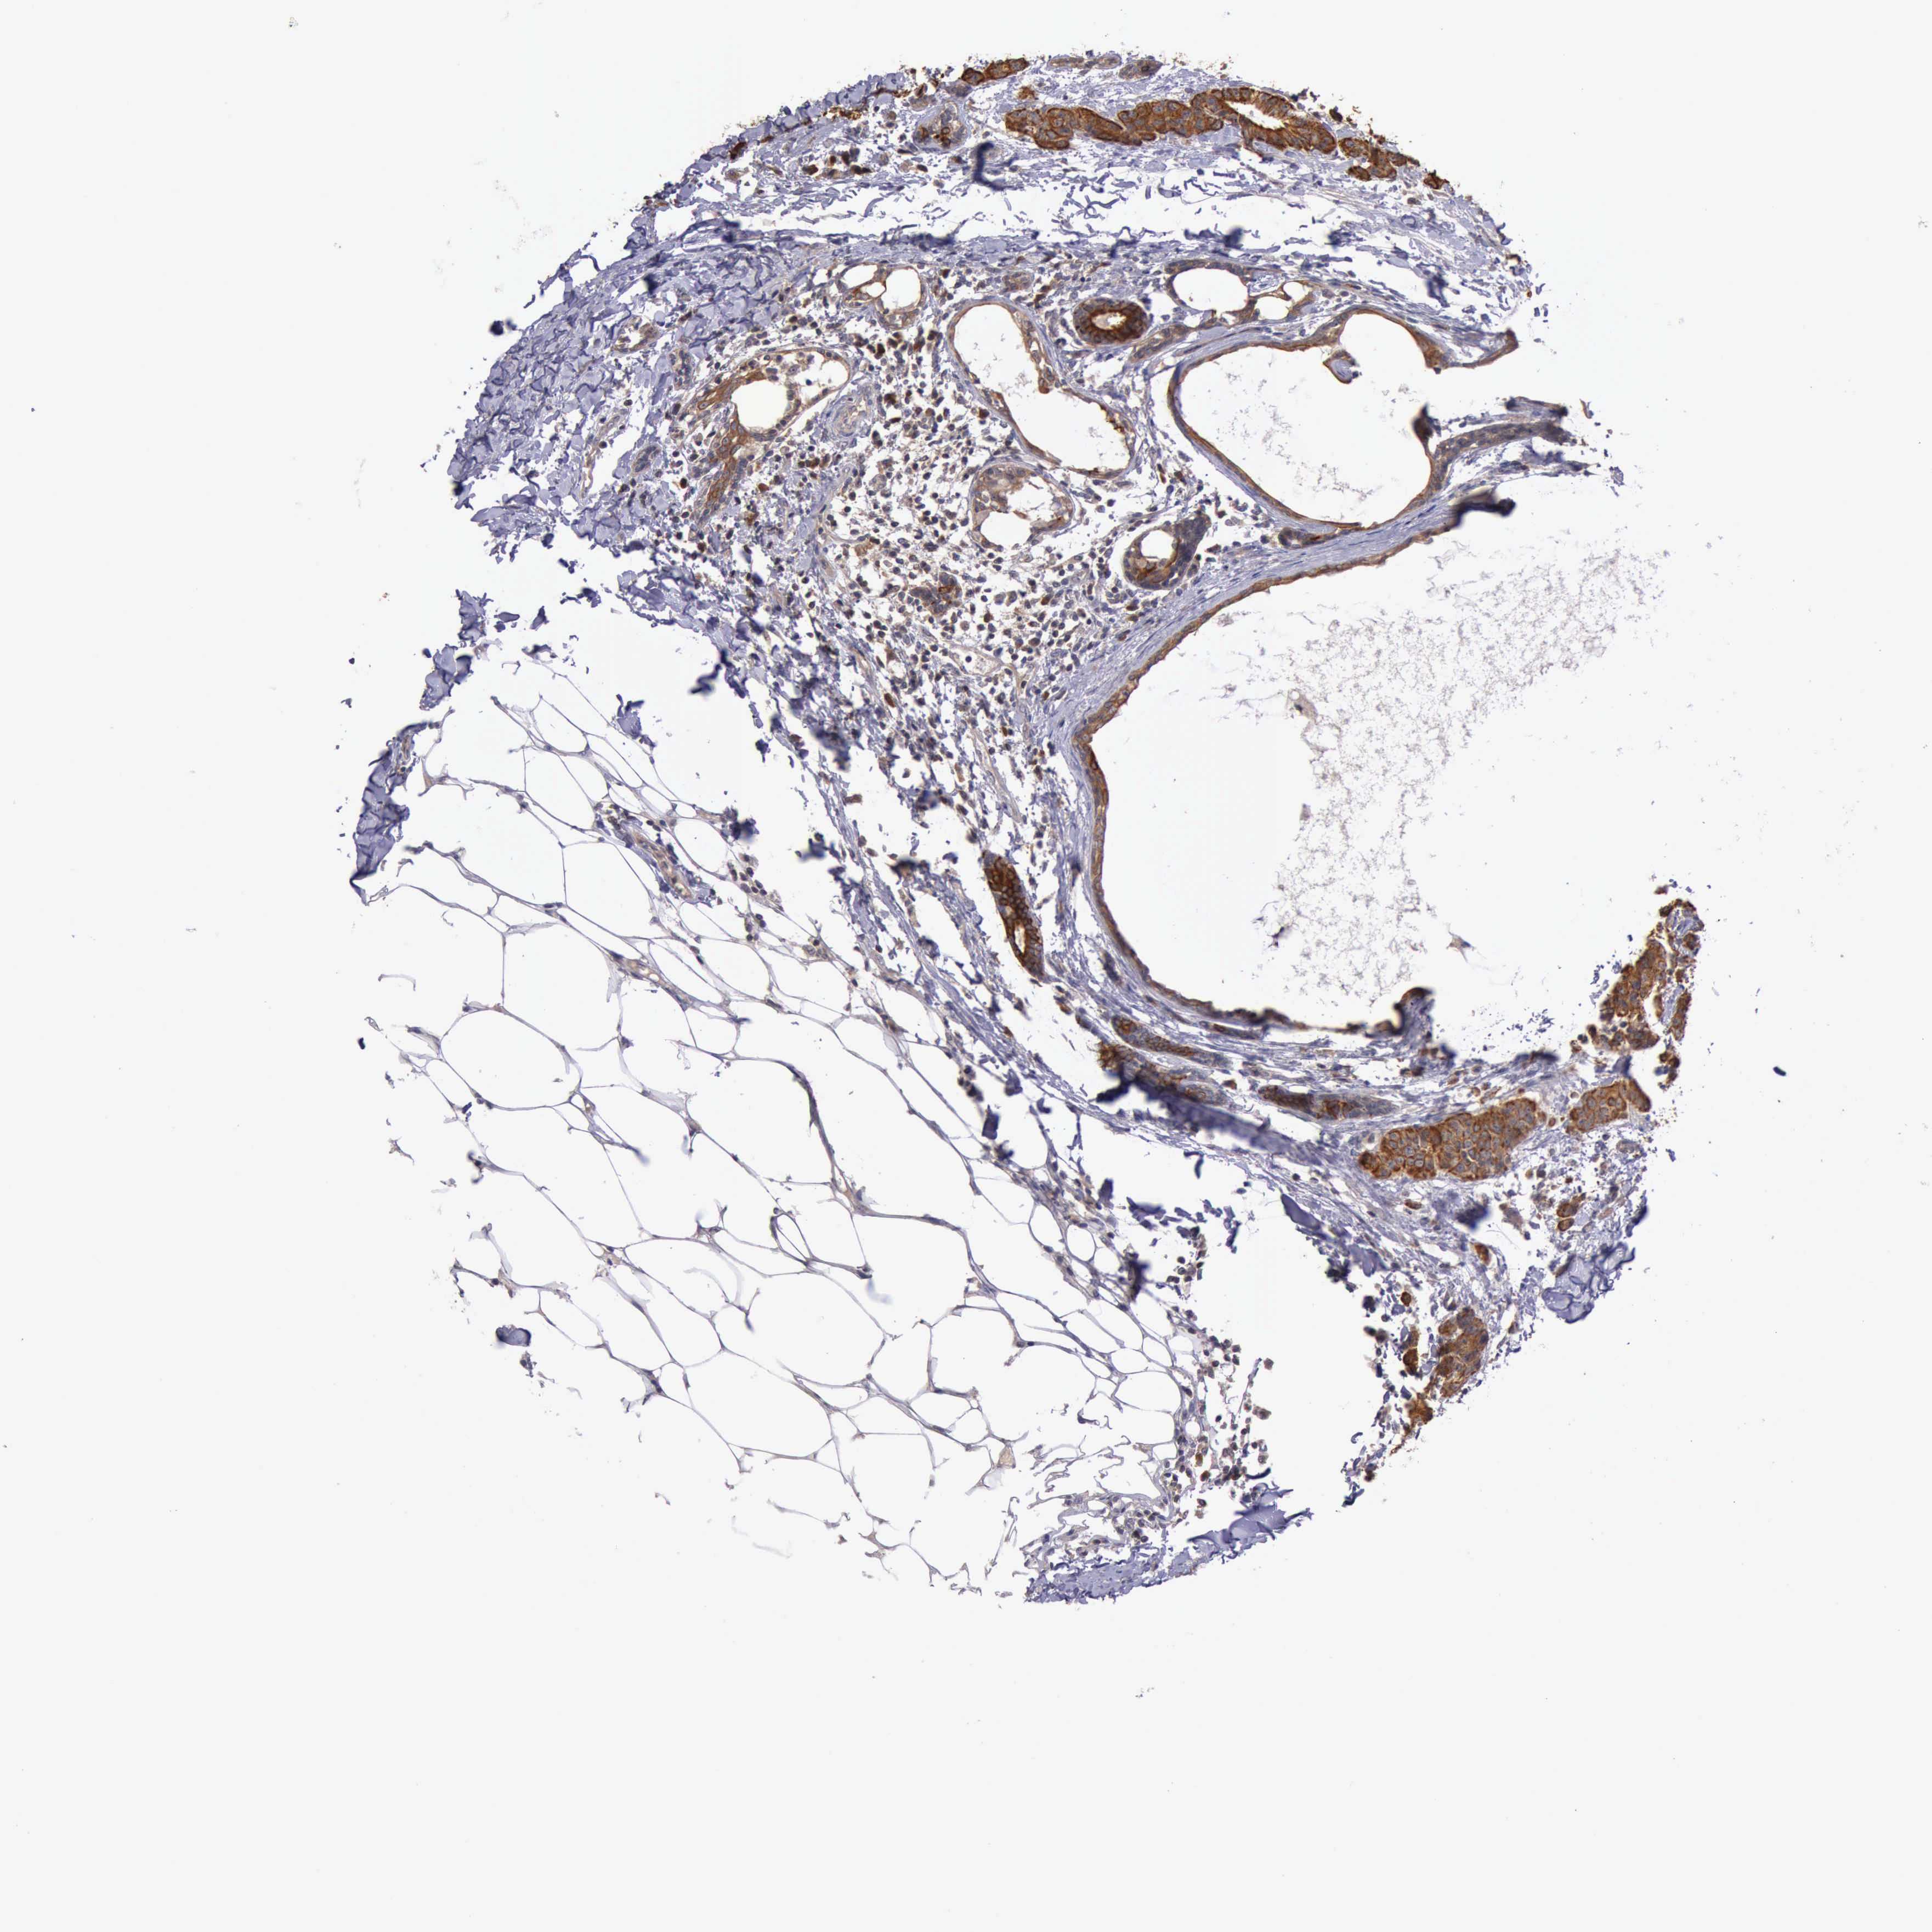

CANCER BREAST CANCER Show tissue menu

BRCA TCGA BRCA VALIDATION PROTEIN EXPRESSION

ANTIBODIES

AND

VALIDATION